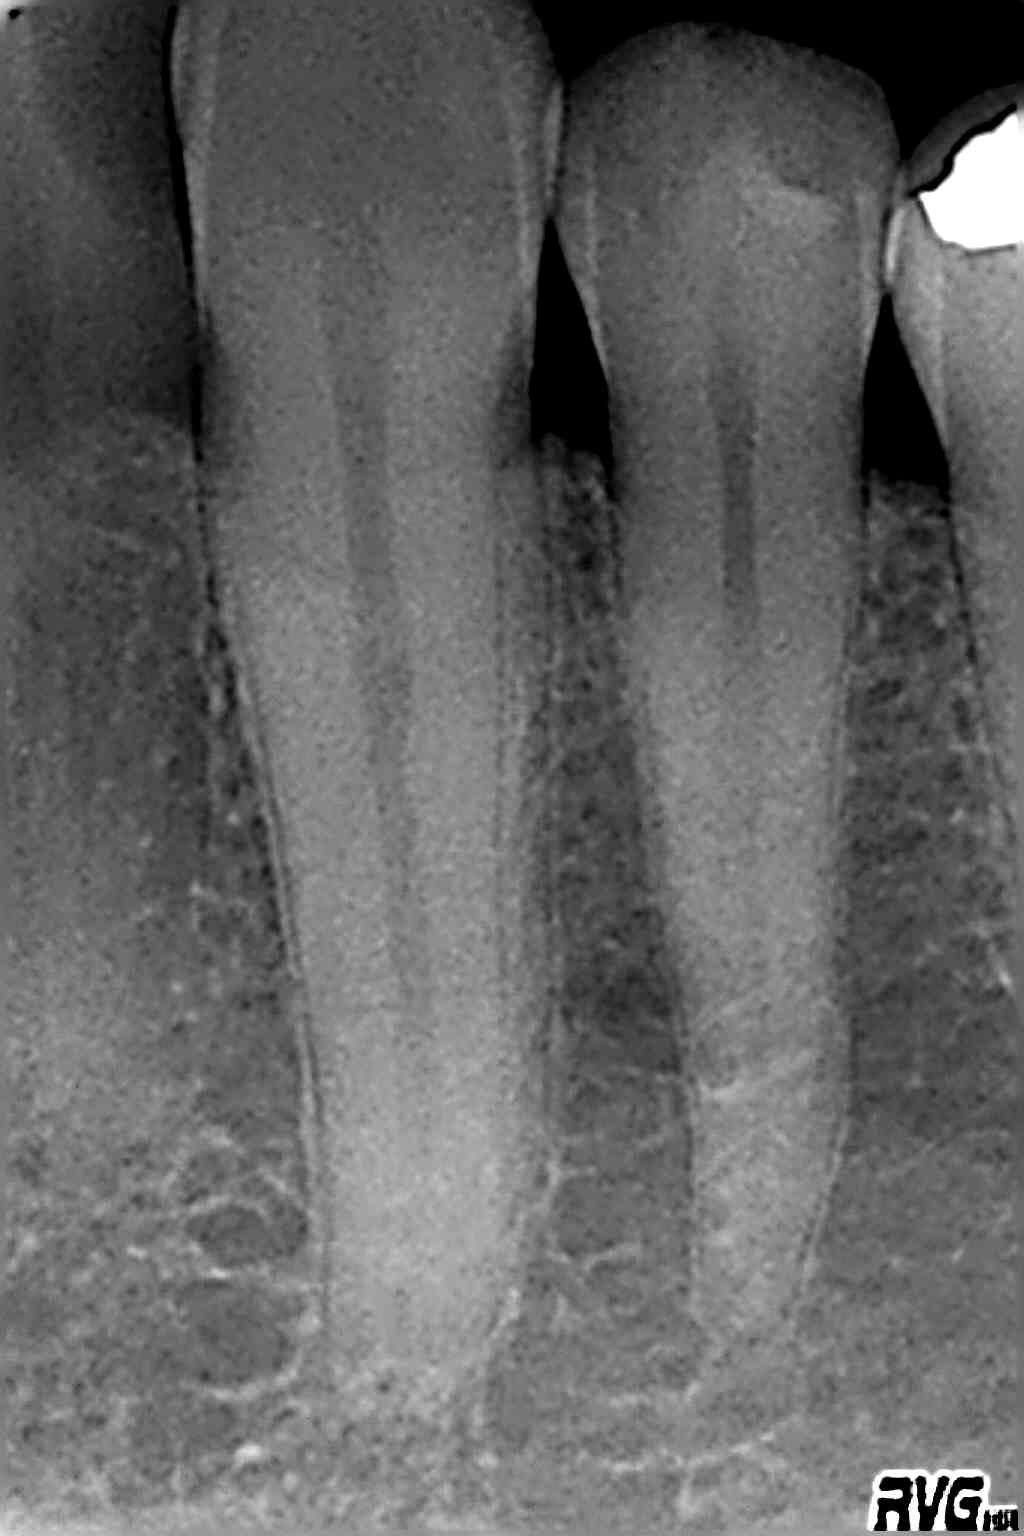

Digitales Röntgen

Röntgenaufnahmen als Einzelaufnahmen wie auch Übersichtsaufnahmen des ganzen Kiefers werden in unserer Praxis digital erstellt.

Die Strahlenbelastung gegenüber herkömmlichen Röntgenaufnahmen ist deutlich reduziert. Die Diagnostik verbessert.

Da keine Entwickler und Fixierbäder benötigt werden ist die Umwelt entlastet.